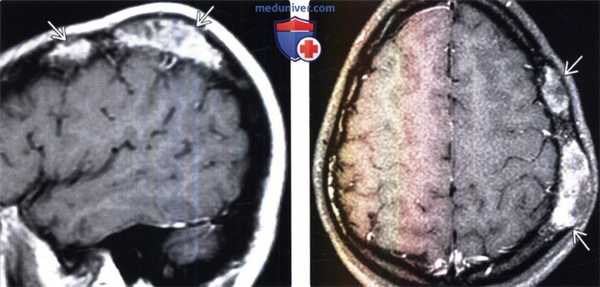

(Слева) МРТ, постконтрастное Т1-ВИ, сагиттальный срез: у этого же пациента определяется два поражения свода черепа, умеренно интенсивно, но гетерогенно накапливающие контрастное вещество.

(Справа) МРТ, постконтрастное Т1 -ВИ, режим подавления сигнала от жира, аксиальный срез: интенсивное, но гетерогенное контрастное усиление поражений. Данные рентгенологические признаки характерны для активной фиброзной дисплазии.